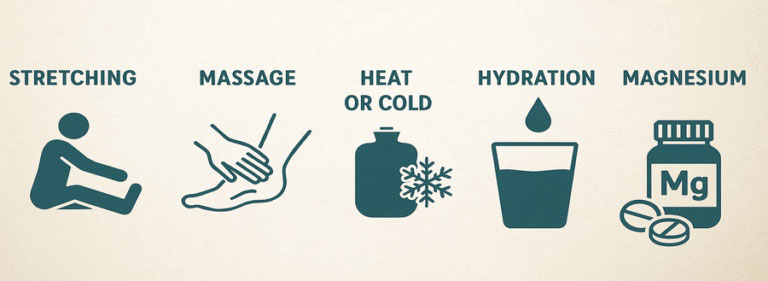

درمان های خانگی برای گرفتگی عضلات

برخی اقدامات ساده در منزل میتوانند به کاهش شدت گرفتگی عضلات کمک کنند. استفاده از کمپرس گرم یا سرد بسته به شرایط، میتواند درد را تسکین دهد.

نوشیدن آب کافی و انجام حرکات کششی سبک نیز از روش های موثر خانگی هستند. با این حال، در صورت تکرار مداوم اسپاسم، مراجعه به فیزیوتراپی برای بررسی تخصصی ضروری است.

-

مصرف مایعات کافی در طول روز

-

استفاده از کمپرس گرم برای شل شدن عضله

-

استراحت کوتاه پس از فعالیت شدید

-

انجام کشش ملایم پس از گرفتگی